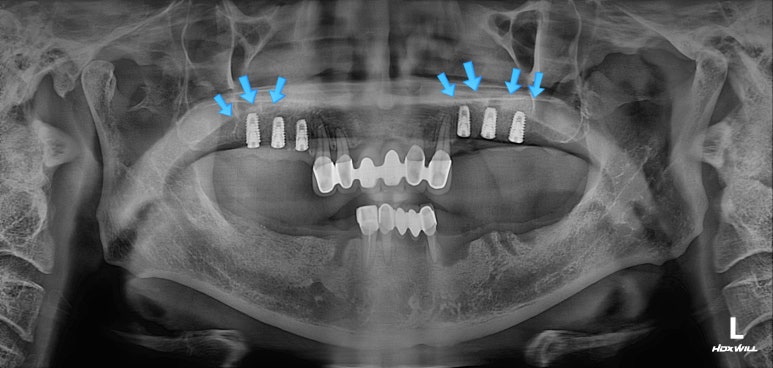

양쪽 위 어금니 부위에 깔끔하게 3개씩 임플란트를 심어드렸습니다.

이 3개의 임플란트는 시간이 흘러 첫번째, 두번째 작은 어금니 그리고 첫번째 큰 어금니가 됩니다.

치과용 파노라마 사진 상에서 잘 확인하기 어려우실 수 있지만,

화살표로 표시해둔 곳까지 측방접근법 상악동 뼈이식술이 성공적으로 잘 된 것을 확인할 수 있습니다.

아무래도 임플란트 수술을 많이 하다보니, 상악동 뼈이식술을 받으시는 분들이 많은데요,

저희 치과는 성공적인 상악동 뼈이식술을 위해 PIEZO SURGERY를 병행하고 있는 곳입니다.